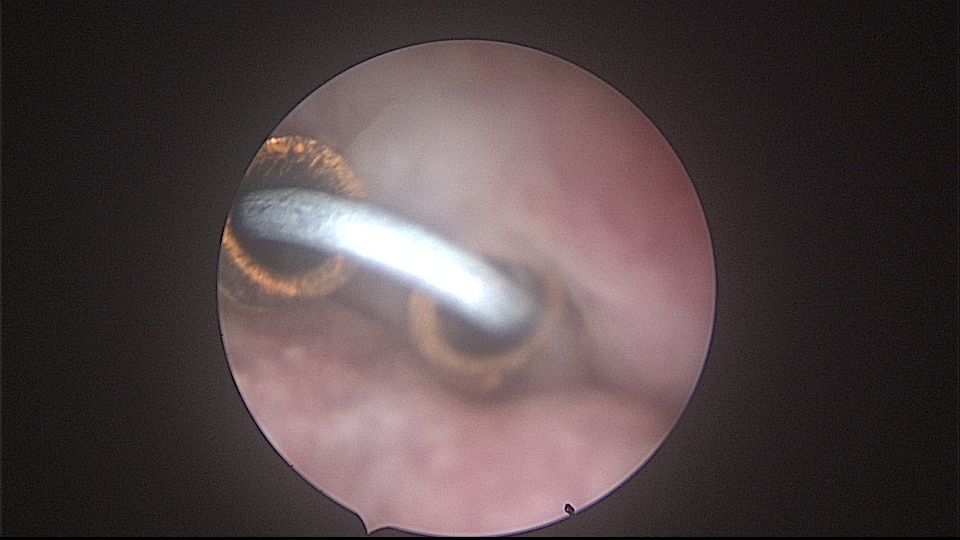

患者52岁,G2P1,顺产1次。安环27年,外院取环失败。病人肥胖,子宫极度前倾前屈位,宫腔镜见宫颈管组织杂乱,宫颈管上段右前壁见假道,膨宫不良,视野模糊,寻找宫腔方向困难,准备B超监护过程中,拆走扩阴器,腹部下压子宫,终于寻找到了宫颈内口,看到了爱母环下端,异物钳牵拉出节育环,再次探查宫腔,无其他异常。